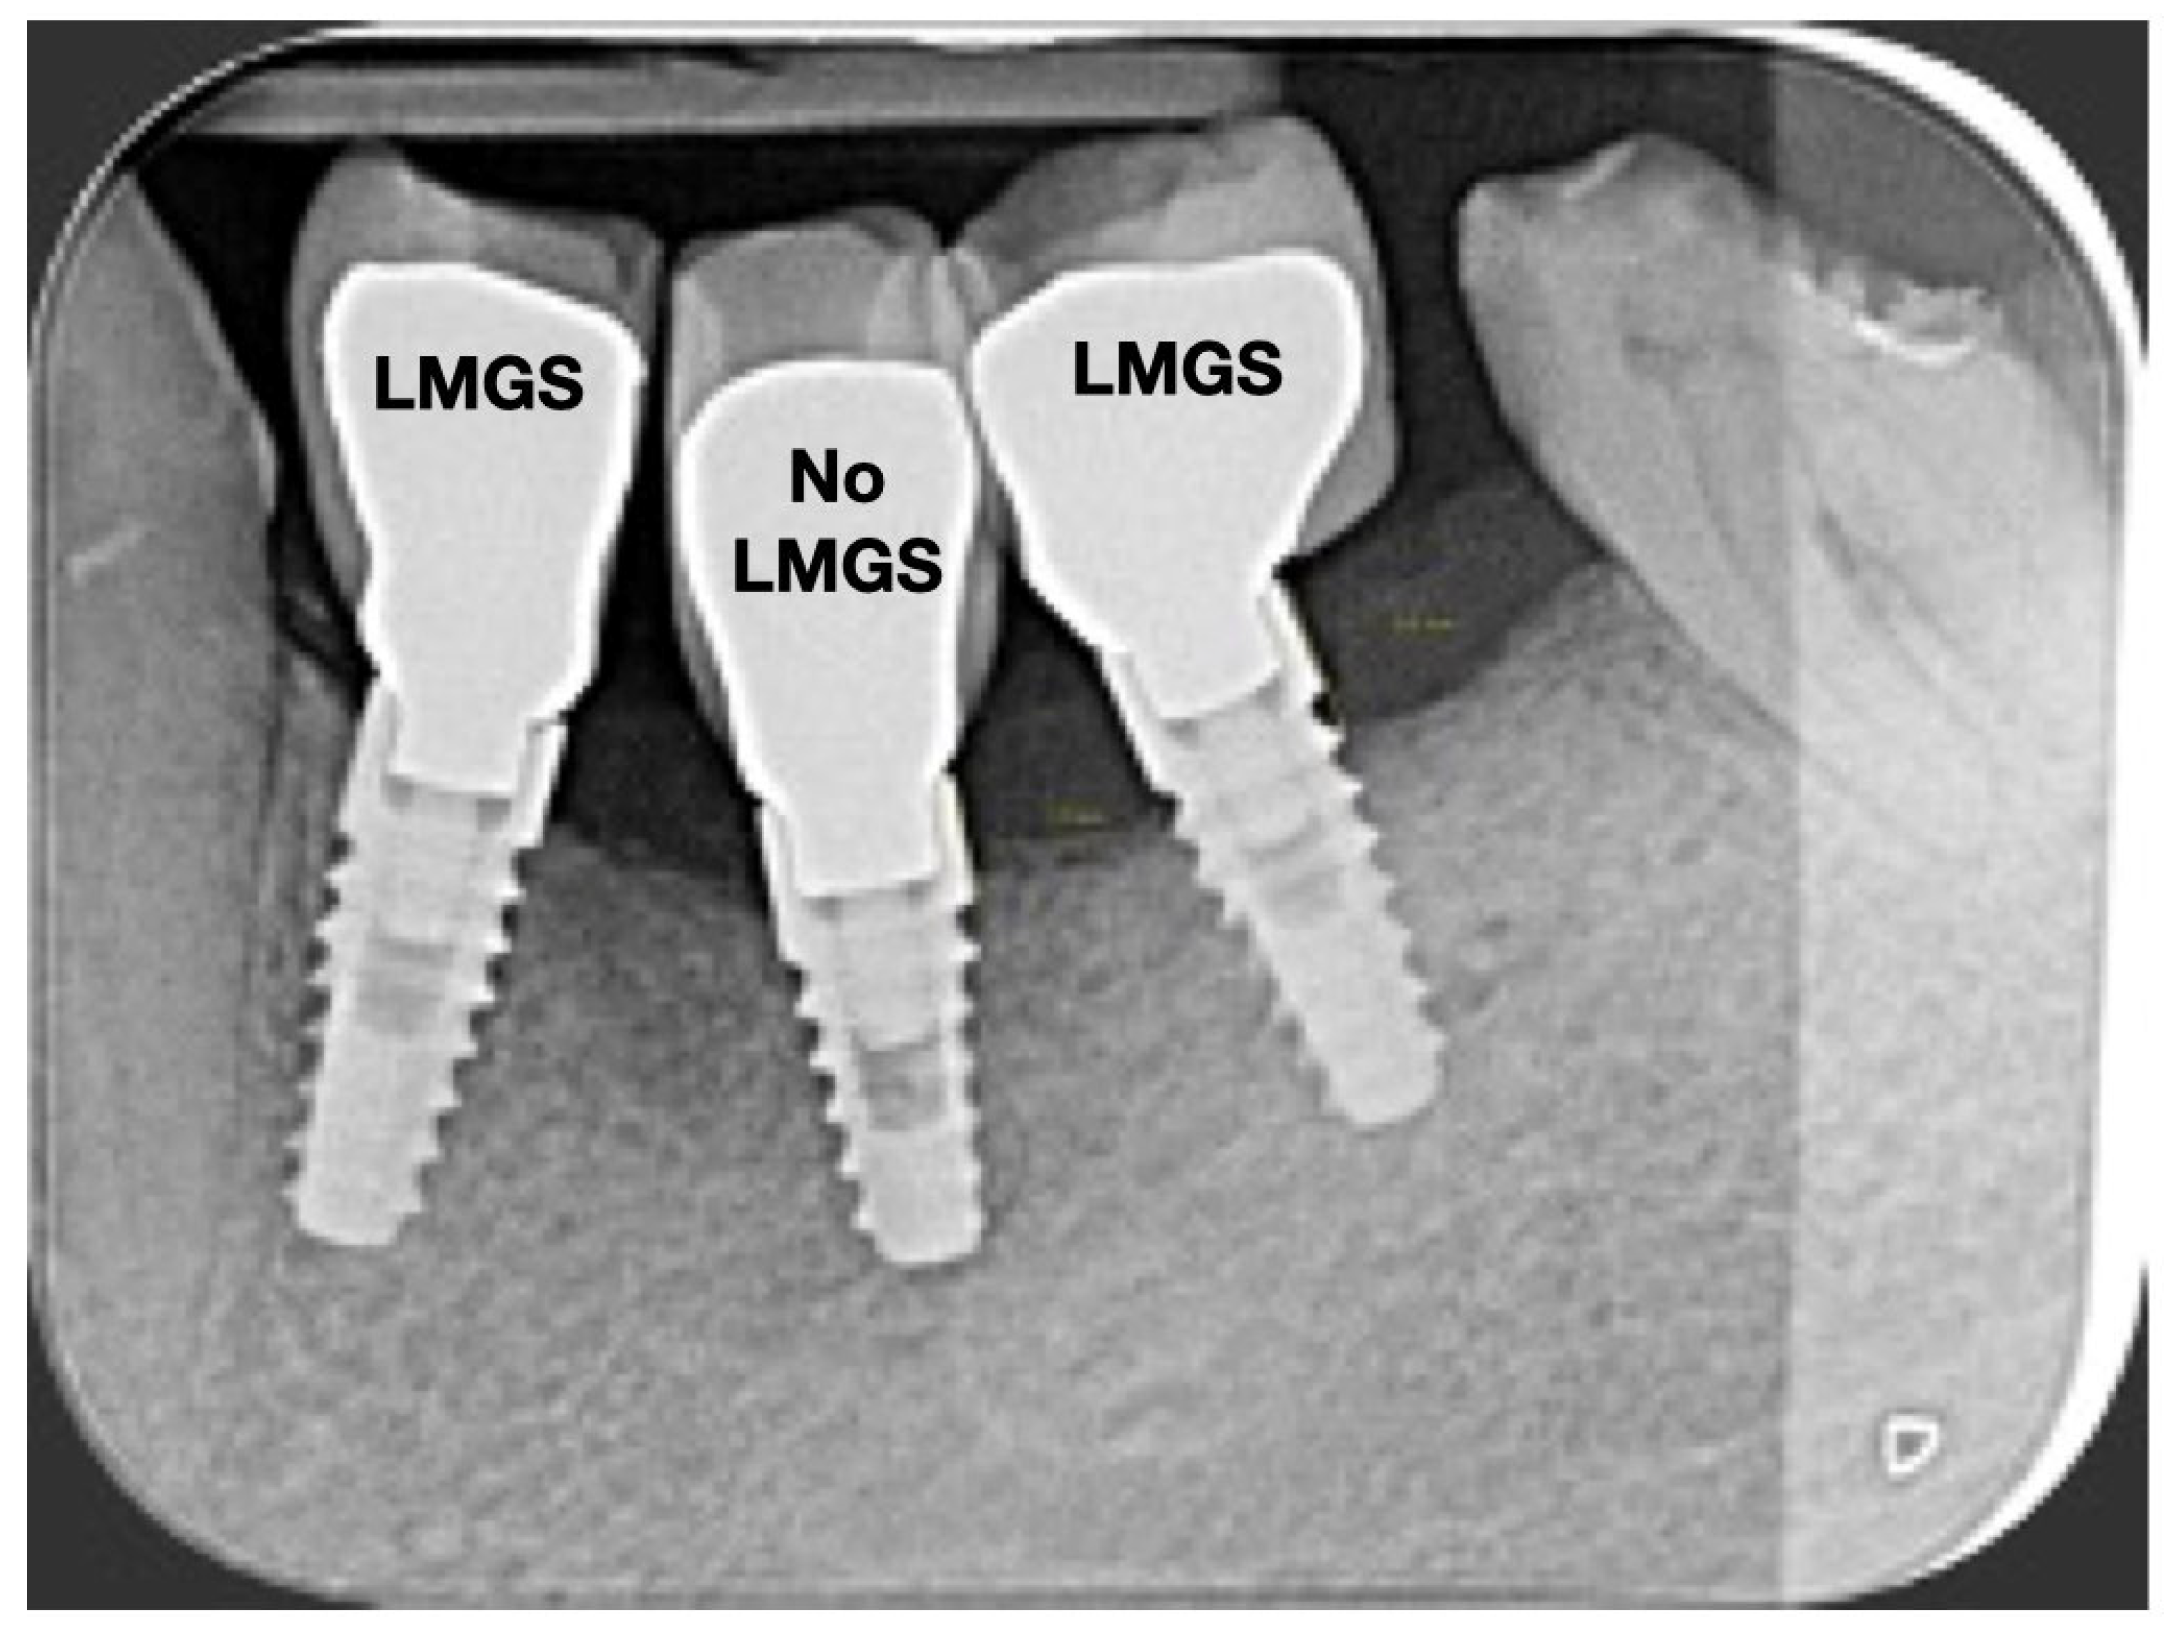

A total of 164 LMGS implants (37.4%) and 195 no-LMGS implants (42.1%) presented PIM. Differences between LMGS implants and no-LMGS implants were not statistically significant (p > 0.05). A total of 28 (6.3%) LMGS implants and 98 (21.1%) no-LMGS implants demonstrated P with a statistically significant difference (p < 0.01). Figure 2, Figure 3, Figure 4 and Figure 5 report examples of radiographs during follow-up.

Figure 2.

Radiograph of three (3) implants at crown delivery. (LMGS = with a laser-microgrooved collar surface; No-LMGS = without a laser-microgrooved collar surface).